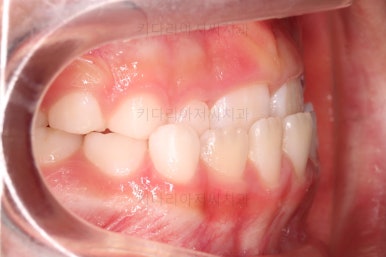

1. 초진

부산어린이교정 키다리아저씨치과에 처음 내원했을 당시의 입안의 모습입니다.

앞니가 거꾸로 물리는 전형적인 앵글씨 3급 부정교합 환아의 모습이었습니다.

아직 유치가 많이 남아 있었꼬, 아래 앞니는 4개가 영구치 맹출, 윗니는 2개가 영구치 맹출 상태였습니다.